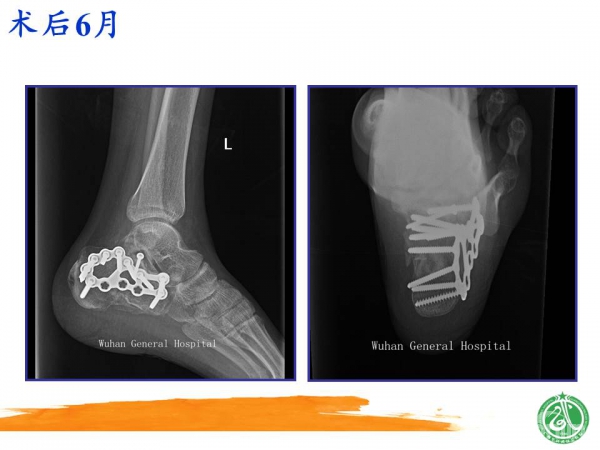

2015-01-12 文章来源:广州军区武汉总医院骨科 魏世隽 我要说